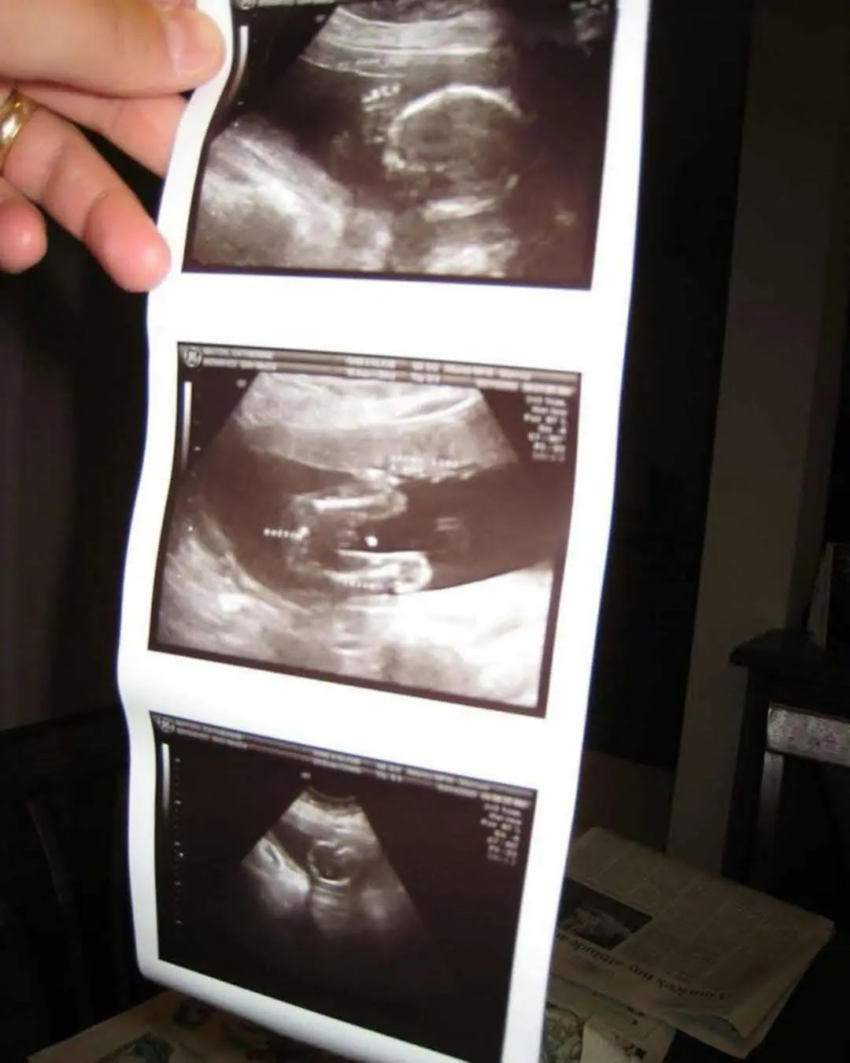

But the moment she handed it over, I felt I was losing consciousness. It wasn’t any space photo. It was an ultrasound picture with “Hi Daddy, I’m coming soon. T ” written on it. Just like that, my world flipped upside down.

Their 5-year-old daughter, Emma, excitedly rummaged through Jack’s suitcase, searching for souvenirs, when she found something unexpected—a mysterious ultrasound photo. Initially dismissing it, the mother was shocked when she noticed a handwritten message: “Hi Daddy, I’m coming soon. —T .”